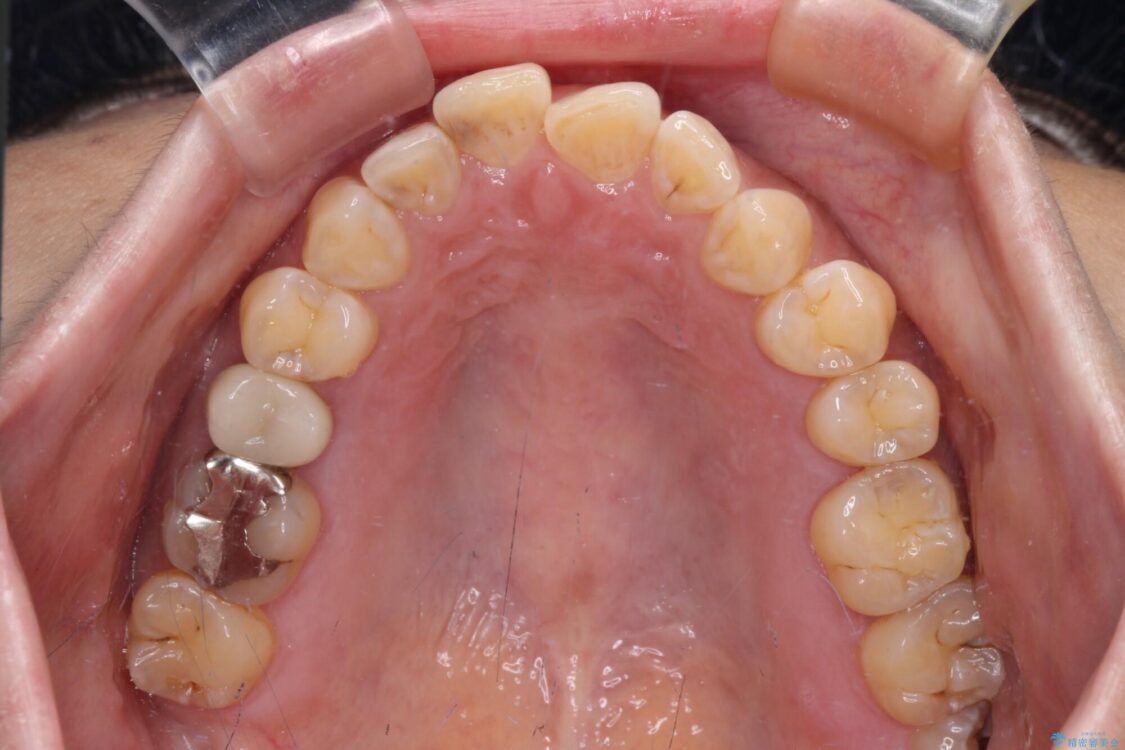

飛び出た上の前歯を気にして来院された患者様です。

奥歯の咬み合わせは、上顎歯列が理想的な一よりも数mm前方にある状態でした。

治療前

• 【モニター】飛び出た前歯を整えたい ワイヤー矯正治療 治療前画像